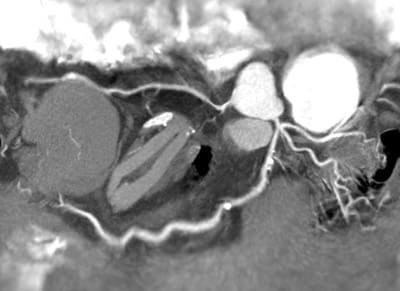

The need for speed continued to push CT machine designers, especially in the medical area. CT scanners for imaging the heart are especially challenging, because of the natural motion of the beating heart. This procedure, known as Cardiovascular Computed Tomography Angiography (CCTA) is a growing application. In this case, the X-ray equipment needs to get around the heart between beats, while the heart is at rest, in order to image the fine blood vessels feeding blood to the heart muscle itself (Figure 2). There are only two options: slow down the heart through sedation or speed up the rotation of the machine.

Philips Healthcare, a major supplier of CT equipment began a new machine design with a fresh sheet of paper in order to find a way to speed up the rotation. According to Philips Healthcare CT Product Manager Robert Popilock, their clinical partners were “interested in performing CT examinations of the heart, requested a system capable of faster rotation speed to improve the likelihood of capturing a “snapshot” (Figure 3) of the vessels supplying blood to the heart wall at the most quiet state.1 ” The solution they found also solved many of the other problems of building precision CT scanning equipment.